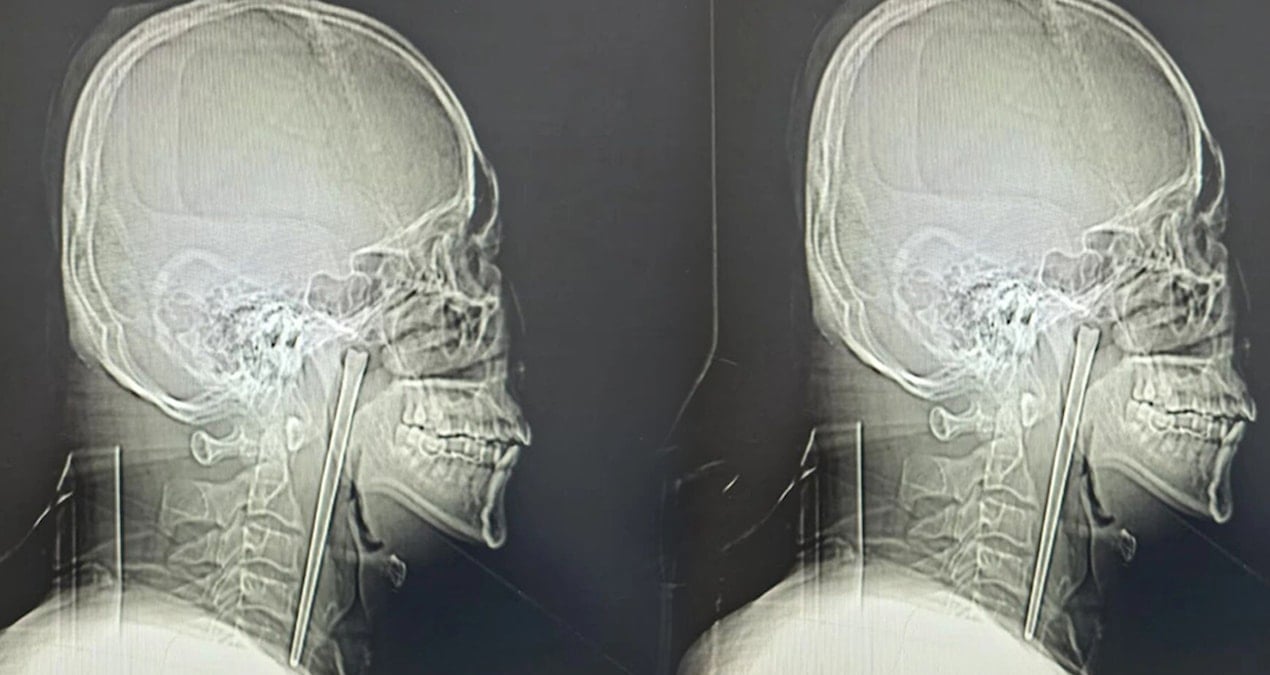

Dalian Belediye Merkez Hastanesi’ne boğazında şiddetli ağrı ve yabancı cisim hissi şikayetiyle giden Bay Wang’ın yapılan röntgen muayenesinde, boğaz bölgesine saplanmış metal bir mil tespit edildi. Hastanın, doktorların sorusu üzerine durumu onaylayarak sekiz yıl önce yemek yerken yanlışlıkla bir metal yemek çubuğu yuttuğunu ifade ettiği bildirildi.

TEK PARÇA HALİNDE ÇIKARILDI

Dalian Teknoloji Üniversitesi Bağlı Merkez Hastanesi Kulak Burun Boğaz Bölümü uzmanları, hayati damarlara ve mukoza dokusuna zarar verme riski bulunan cisim için minimal invaziv (kapalı cerrahi) yöntemini tercih etti. Dr. Huang Weipeng ve ekibi tarafından gerçekleştirilen operasyonla, 12 santimetre uzunluğundaki paslanmaz çelik çubuk dokulardan ayrılarak tek parça halinde çıkarıldı.